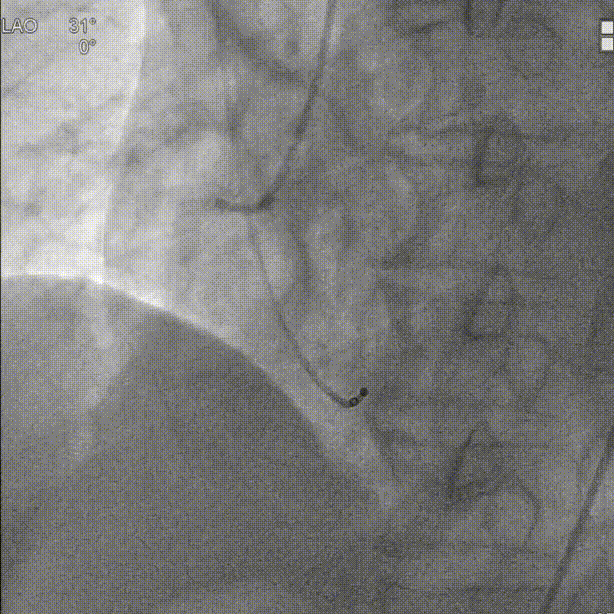

初始定位,左右窦重叠视图开始释放:

释放中期,快速起搏下释放到80%切换视图,并借助食管心超评估深度和反流情况:

完全释放和瓣膜脱钩: